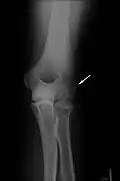

-

Klassische Zuggurtung einer Patellafraktur -

Erweiterte Zuggurtung einer Patellafraktur (mit K-Drähten) -

Eine Bimalleolarfraktur im seitlichen Röntgenbild … -

… und von vorne … -

… mit Zuggurtung am Innenknöchel und Platte am Außenknöchel versorgt